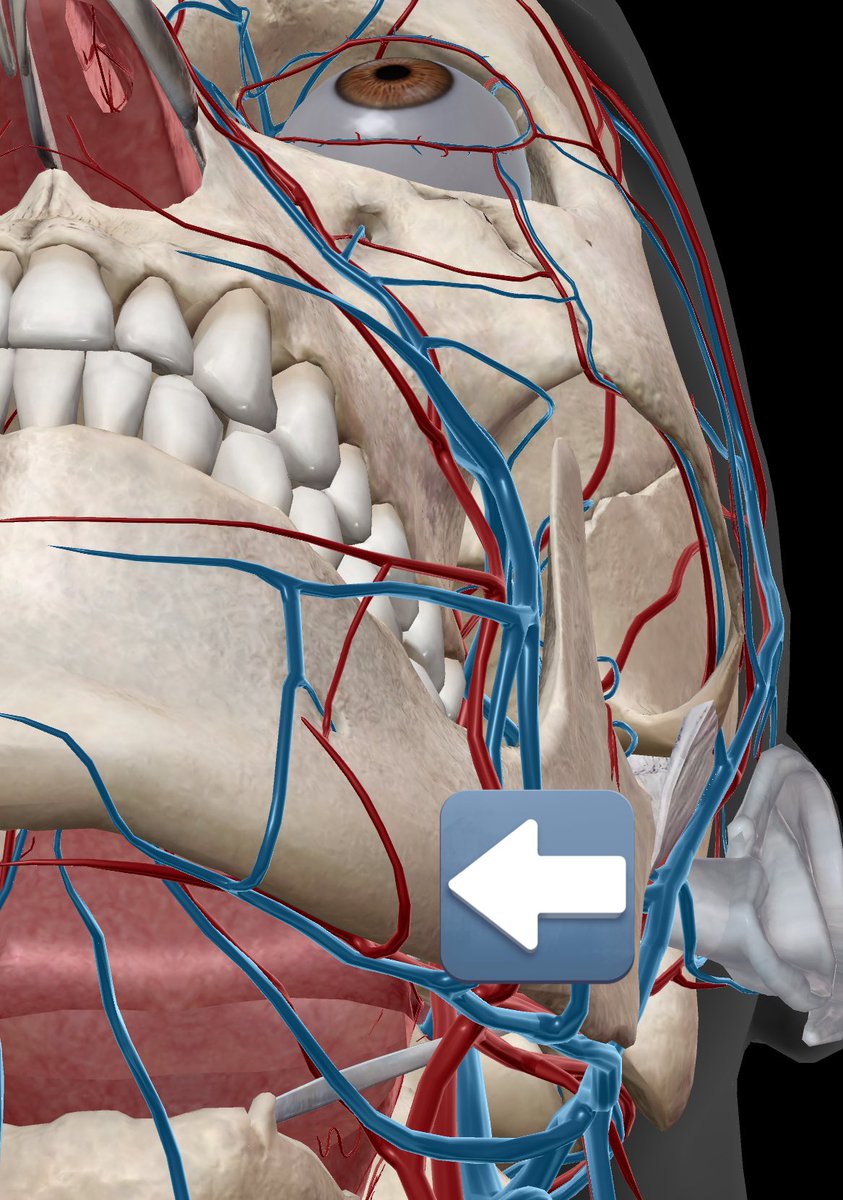

この方の様に、多くの人が誤解しているので整理して解説します。 脂肪吸引後に“命に関わる血腫”として問題になるのは、 顔面動脈の枝(特にオトガイ下動脈)からの“動脈性出血” です。 これは一気に血が溜まるため、場合によっては挿管が困難になります。…

脂肪吸引後に“命に関わる血腫”として問題になるのは、

顔面動脈の枝(特にオトガイ下動脈)からの“動脈性出血” です。

これは一気に血が溜まるため、場合によっては挿管が困難になります。…